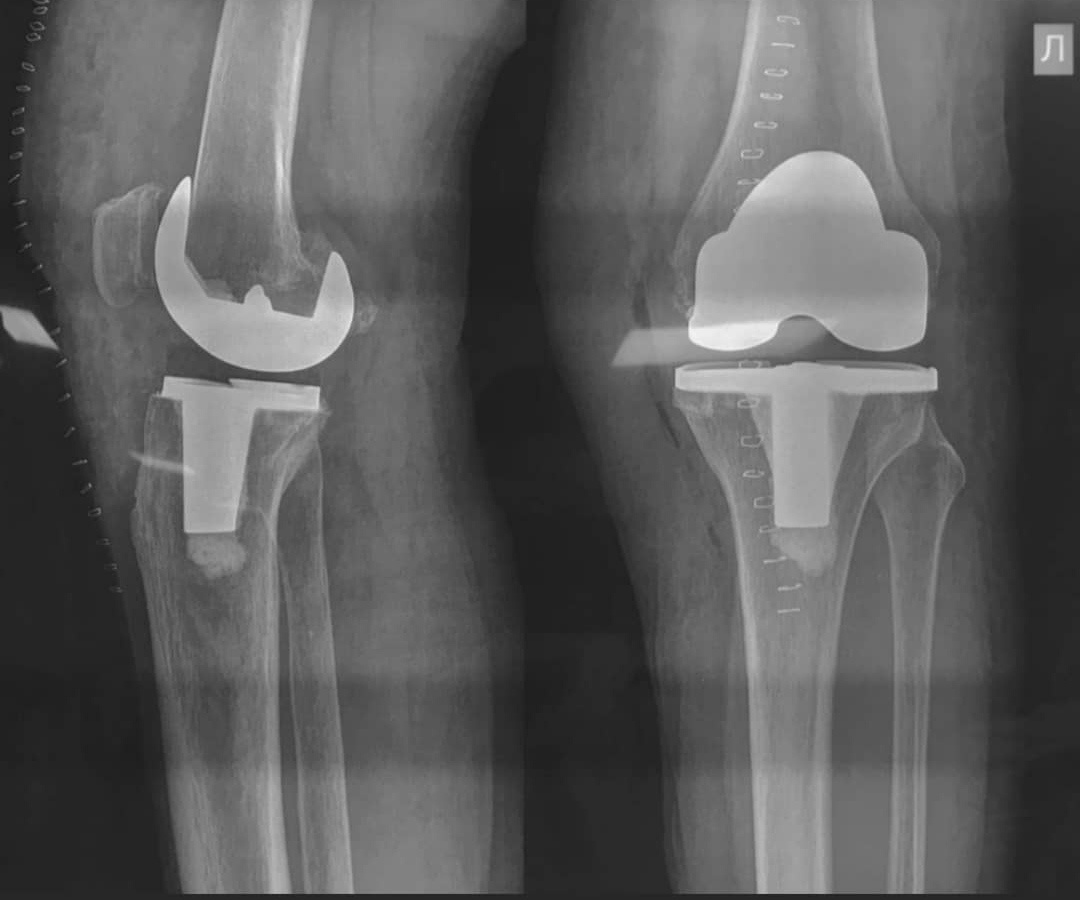

При стадиях артроза, сопровождающихся изменением оси конечности, возможно применение более инвазивных методик, таких как корригирующие остеотомии, вплоть до эндопротезирования сустава.